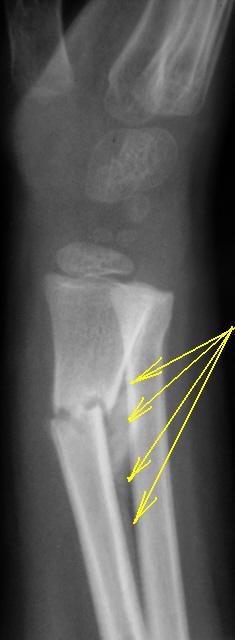

Срастающийся перелом обеих костей предплечья в н/3 с допустимым смещением. Если перелом был бы свежим, можно было бы подправить. А сейчас - можно оставить так как есть, смещение исправится.

Абсолютно уверена, что это костная мозоль, а односторонняя она потому, что есть смещение, всегда мозоль выражена, где открытый угол. Признаков воспаления здесь нет.

А кто может четко сказать перелом консолидировался или нет? То что он "пытается" это понятно, есть асимметричная мозоль, избыточная, но линия перелома остается! Тут критерий сращения - только подвижность в месте перелома. Отдельно лежащий фрагмент может быть скиалогическим феноменом, во всяком случае признаков его некроза нет. А что переломы последние годы перестали срастаться - так это проблема...

Перелом срастающийся потому, что есть костная мозоль. Причем абсолютно нормальная и, как уже указала Ola-la, носит односторонний характер ввиду того, что перелом со смещением. Природа уже начала исправлять то, что не доделали травматологи.

Чётко сказать о том, что перелом консолидирован, можно будет после того, как перестанет прослеживаться линия перелома. Фрагмент будет вовлечён в процесс консолидации и перестроится в нормальную костную ткань. В общем, обычный срастающийся перелом с допустимым смещением